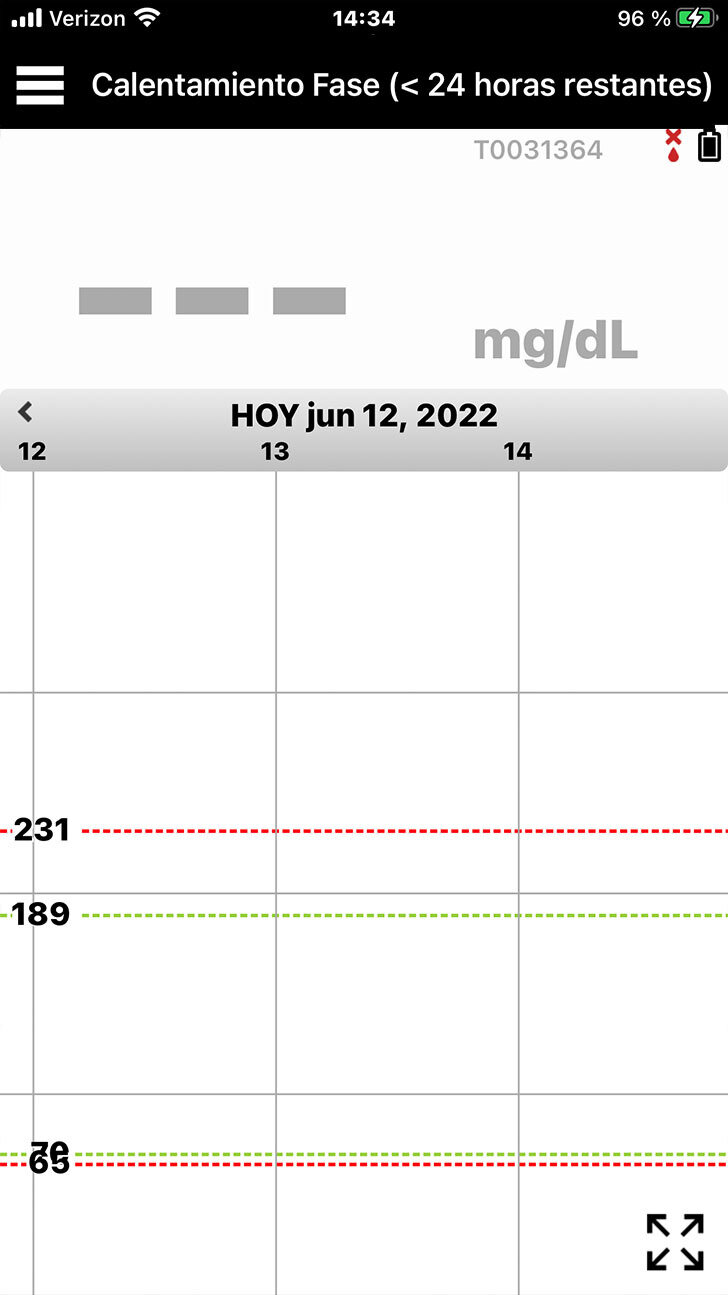

En la pantalla de inicio Mi glucosa, observará que el icono de la batería del transmisor ubicado en la parte superior derecha está en negro.

La barra de estado de la aplicación indicará Fase de calentamiento o No se ha detectado ningún sensor.

CONFIGURE LA APLICACIÓN PARA MÓVIL EVERSENSE

Si no está conectado, el icono

de la batería estará gris y la barra

de estado de la aplicación indicará No hay ningún transmisor conectado.